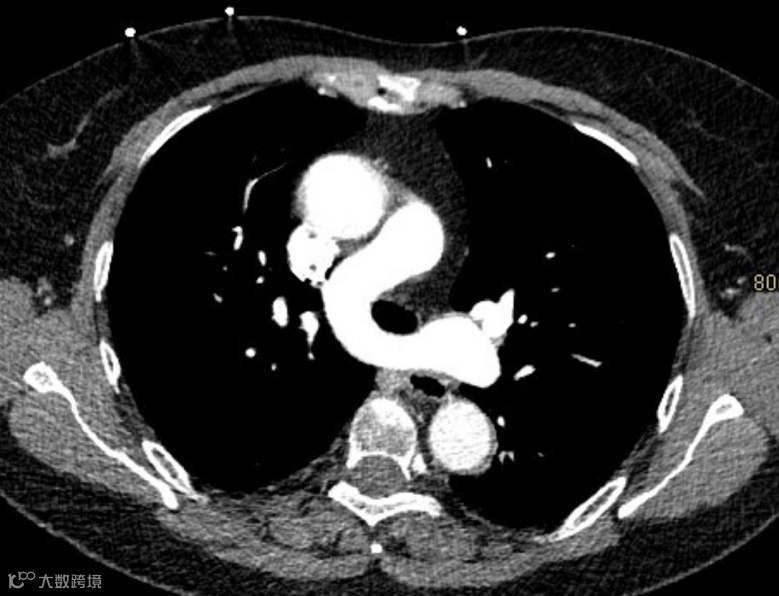

胸部CT增强图像如下:

左肺动脉起源异常,由右肺动脉发出,在气管隆突上方与食管之间形成不完整的环状结构。双肺散在分布多发实变影。

左肺动脉吊带,伴双肺感染